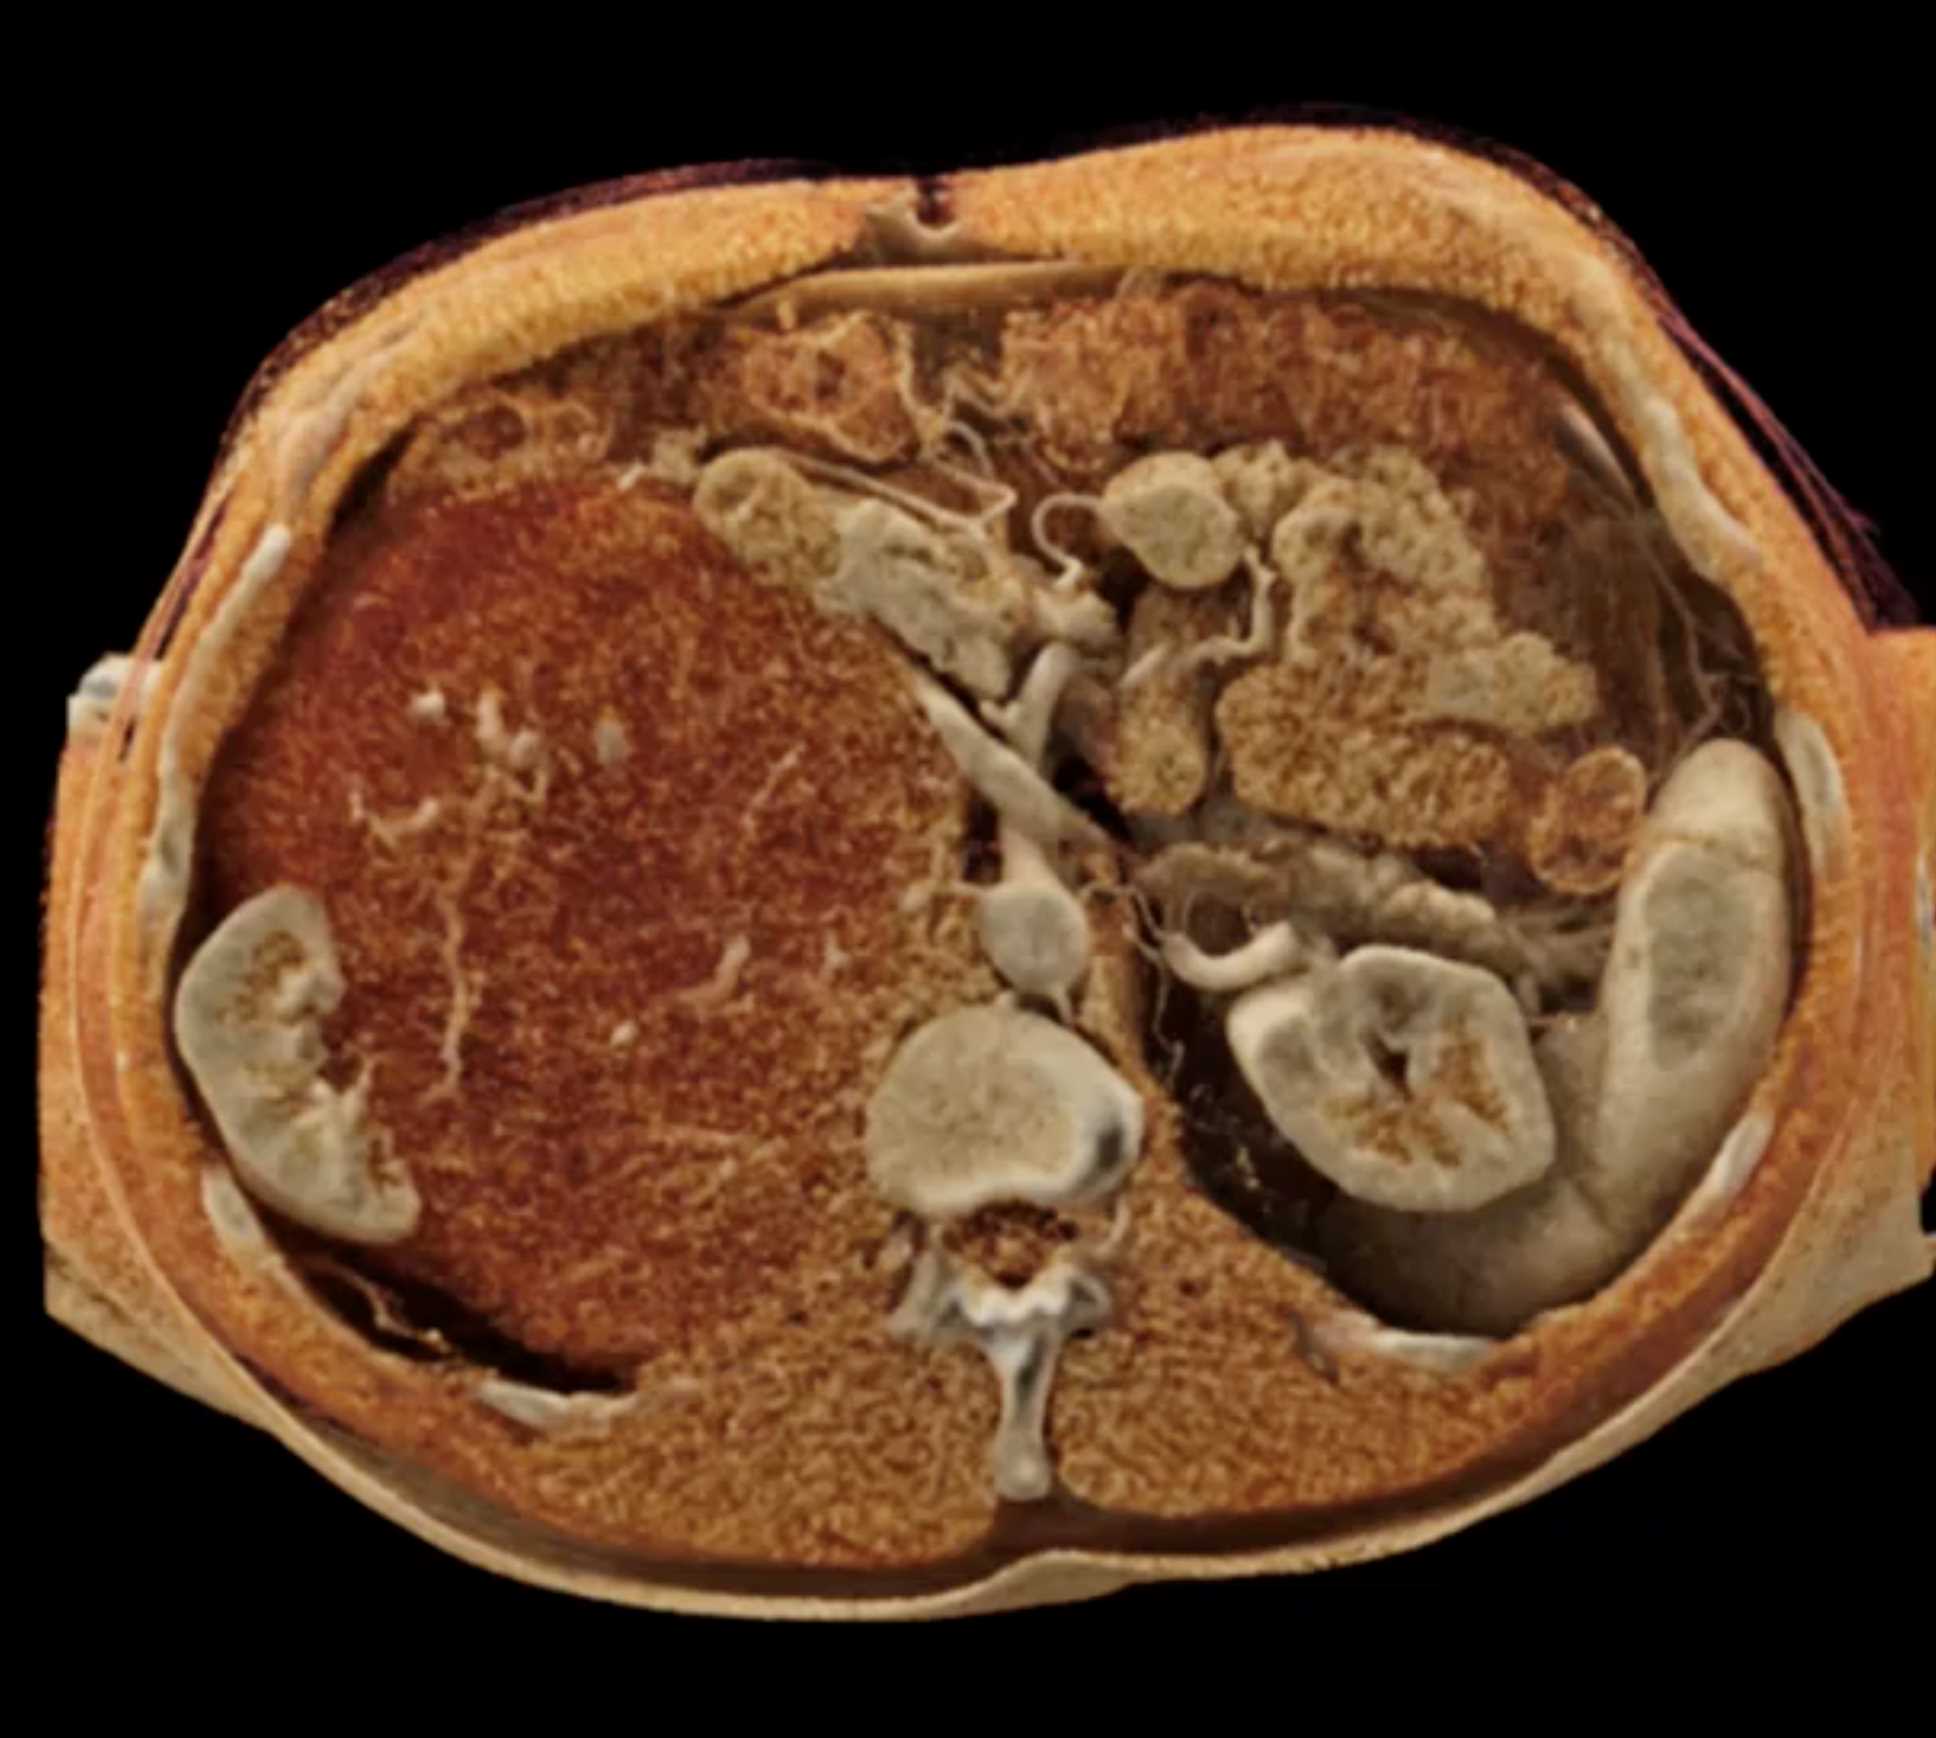

Left Adrenal Metastases from Renal Cell Carcinoma